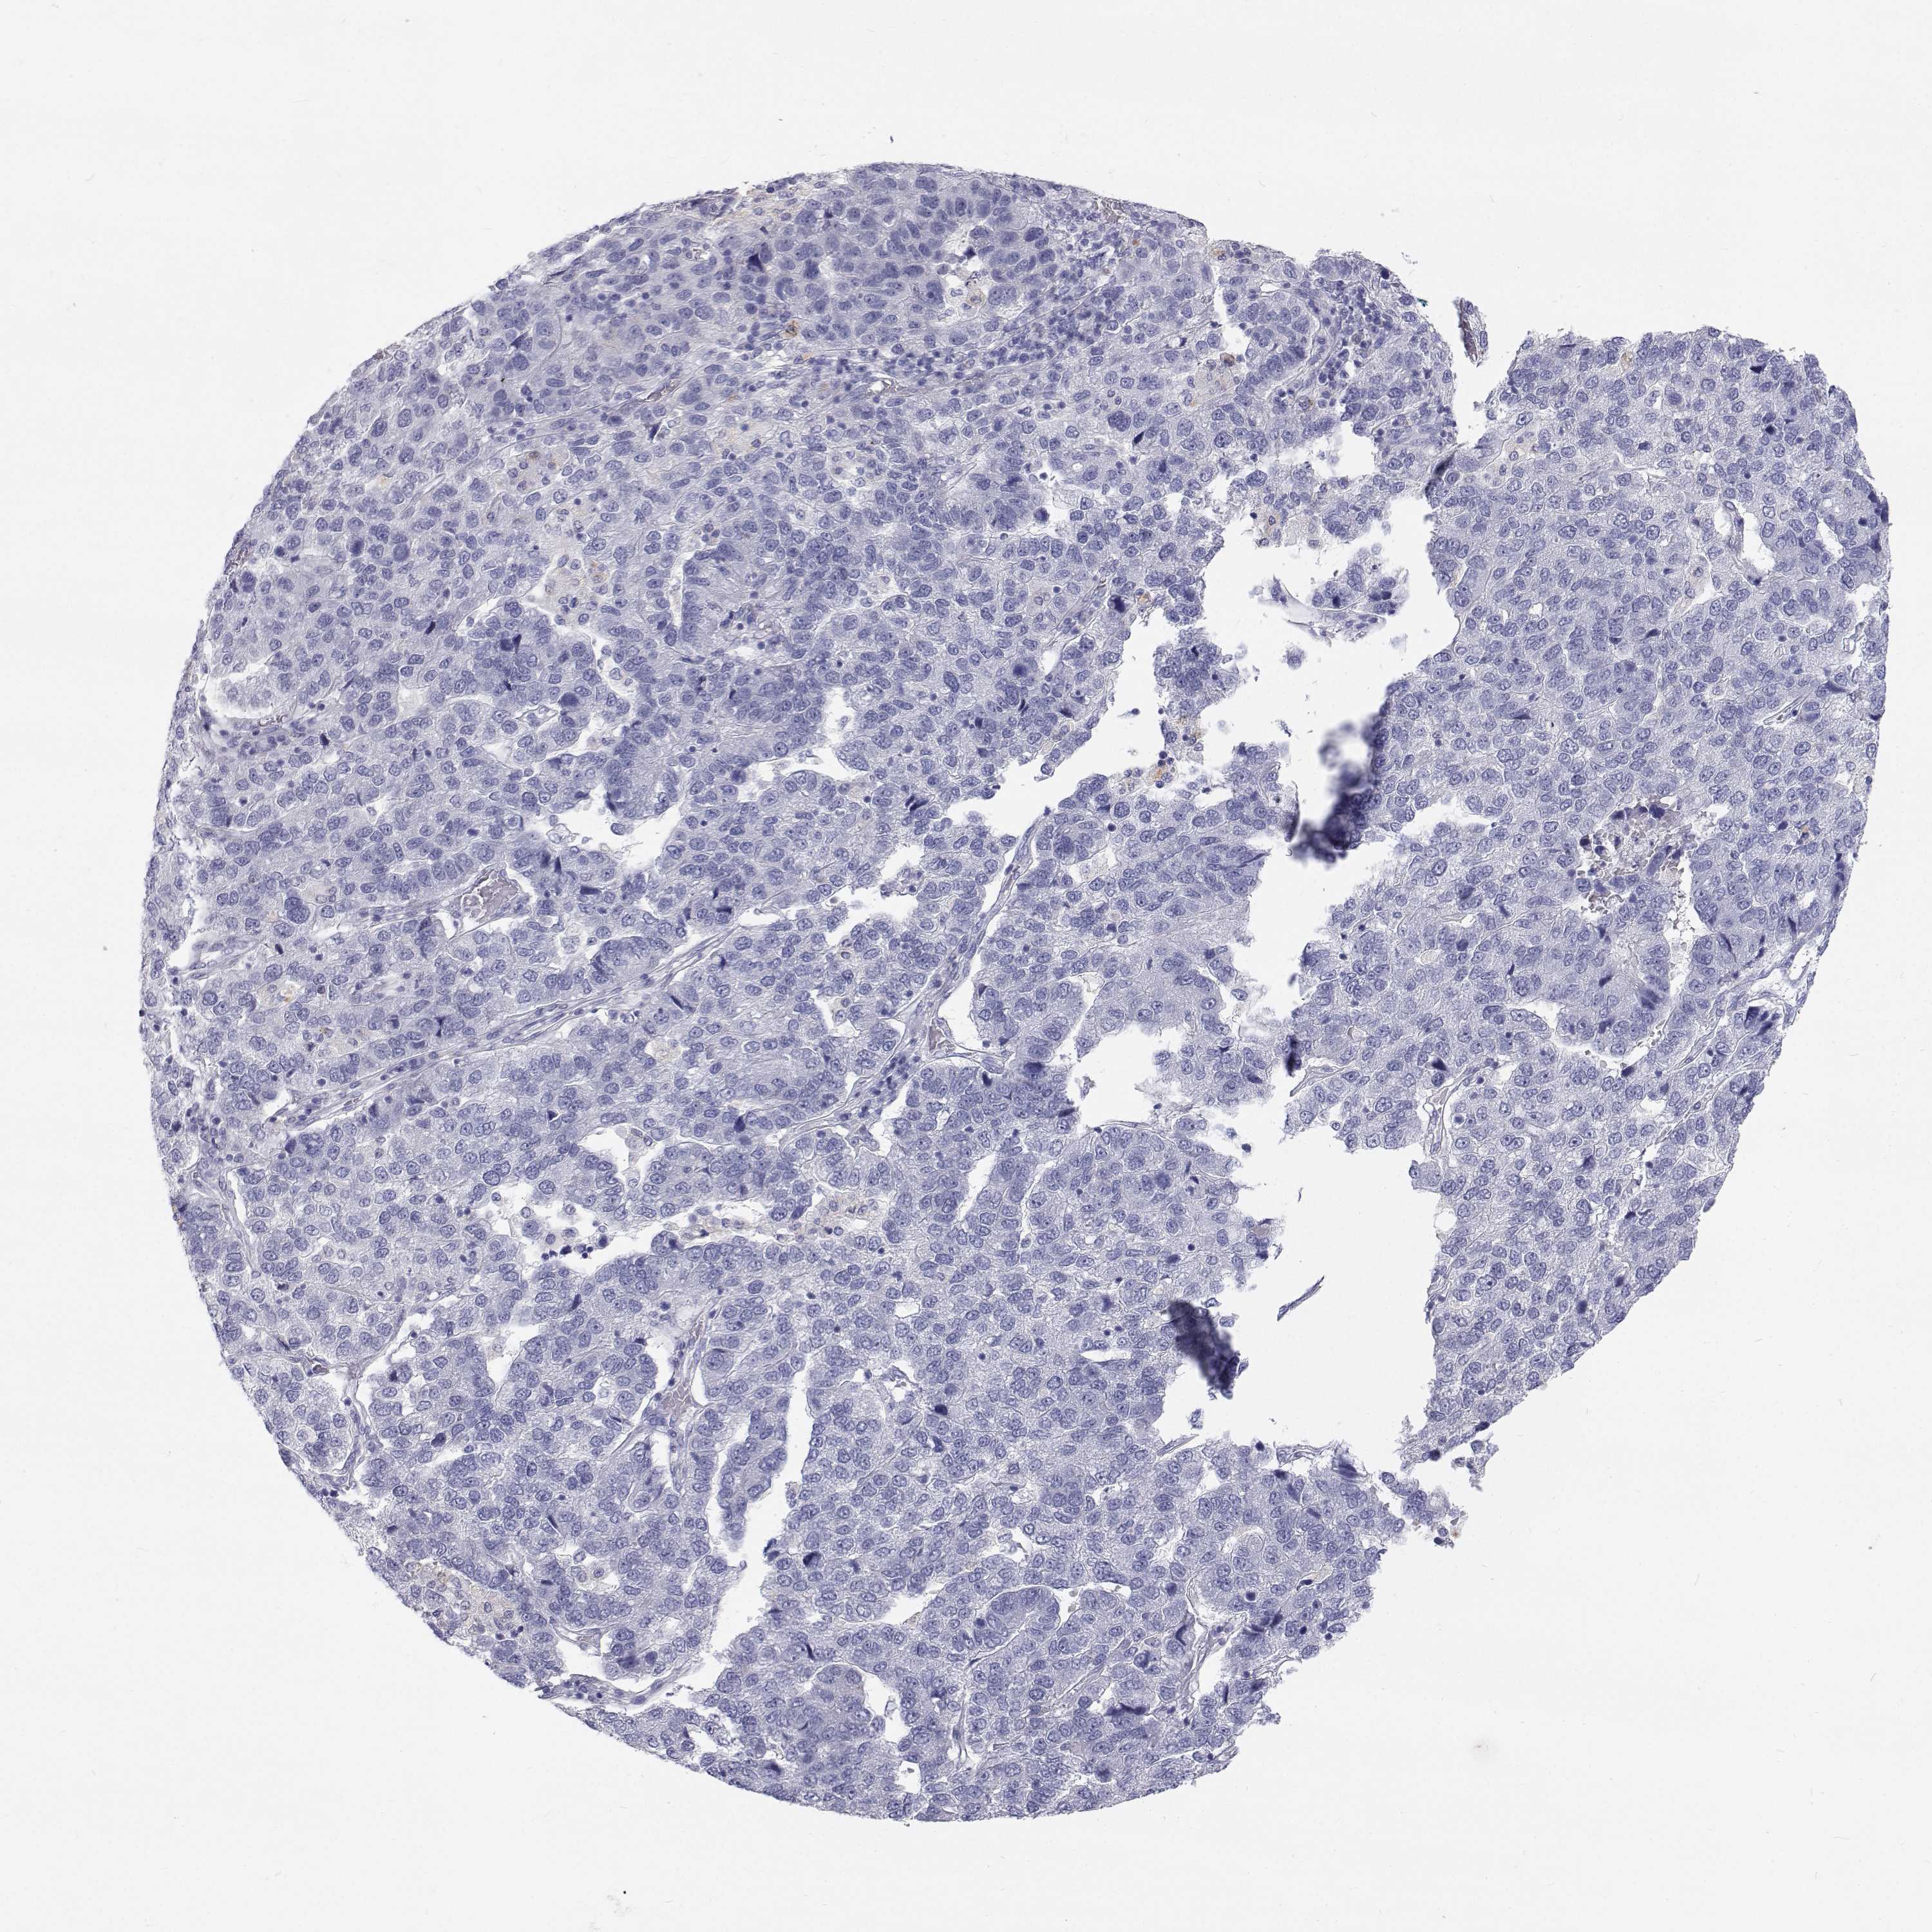

PANCREATIC CANCER - Protein expressioni

A mouse-over function shows sample information and annotation data. Click on an image to view it in a full screen mode. Samples can be filtered based on level of antibody staining by selecting one or several of the following categories: high, medium, low and not detected. The assay and annotation is described here.

Note that samples used for immunohistochemistry by the Human Protein Atlas do not correspond to samples in the TCGA dataset.

Antibody stainingi

Antibody staining in the annotated cell types in the current human tissue is reported as not detected, low, medium, or high, based on conventional immunohistochemistry profiling in selected tissues. This score is based on the combination of the staining intensity and fraction of stained cells.

Each image is clickable and will lead to virtual microscopy that enables deeper exploration of all samples and also displays staining intensity scores, fraction scores and subcellular localization as well as patient and tissue information for each sample.

Antibody HPA067249

Staining

High

Medium

Low

Not detected

Intensity

Strong

Moderate

Weak

Negative

Quantity

>75%

75%-25%

<25%

None

Location

Nuclear

Cytoplasmic/membranous

Cytoplasmic/membranous,nuclear

Adenocarcinoma, NOS